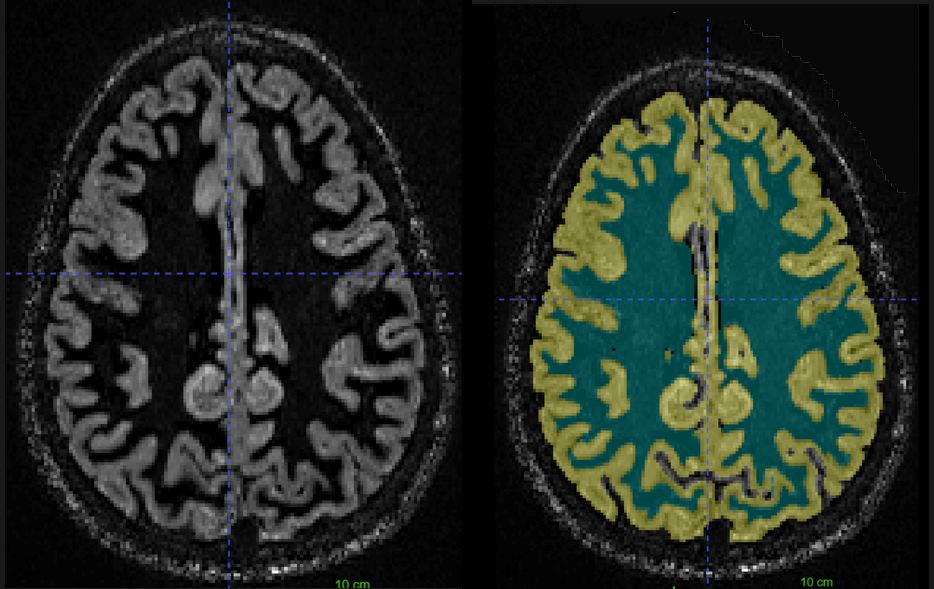

Notre objectif est de développer de nouvelles méthodes de mesure des paramètres indirects basés sur l'IRM et l'optique, ainsi que de rechercher de nouveaux biomarqueurs de manière rapide, robuste, reproductible et fiable, tout en prenant en compte les mouvements physiologiques. Les biomarqueurs recherchés proviennent des propriétés mécaniques, biochimiques ou structurelles des tissus étudiés. Nous aspirons à combiner les innovations basées sur la physique à l'origine de la création d'informations mécaniques, biochimiques ou structurelles, tant du point de vue des stratégies d'acquisition que de l'instrumentation, et à ancrer ces développements dans la pratique clinique.

Nos objectifs scientifiques peuvent être résumés en 4 points principaux : 1) Passer de la preuve de concept réalisée au cours des cinq dernières années à l'application sur des études précliniques et cliniques. 2) Générer et étiqueter les phénomènes physiques derrière les données d'imagerie afin d'intégrer les approches radiomiques et d'apprentissages statistiques. Cet objectif scientifique sera réalisé en étroite collaboration avec l'équipe MYRIAD. 3) Poursuivre les développements en amont dans l'acquisition ou l'instrumentation. 4) Soutenir des projets typiques de l'équipe qui fédèrent plusieurs chercheurs de l'équipe (IRM/optique endoluminale) ou de l'unité (projets transversaux TipTop, IDM4, Tumor-ID, MUSIC). Notre équipe possède une expérience et des connaissances dans de nombreux aspects appliqués de la résonance magnétique, allant de la théorie de la physique de l'IRM à la validation médicale et aux applications. Forts de cette expérience, et sachant que la résonance magnétique joue souvent un rôle central dans de nombreuses investigations en imagerie biomédicale, les membres de notre équipe sont impliqués dans la plupart des projets transversaux et inter-équipes.